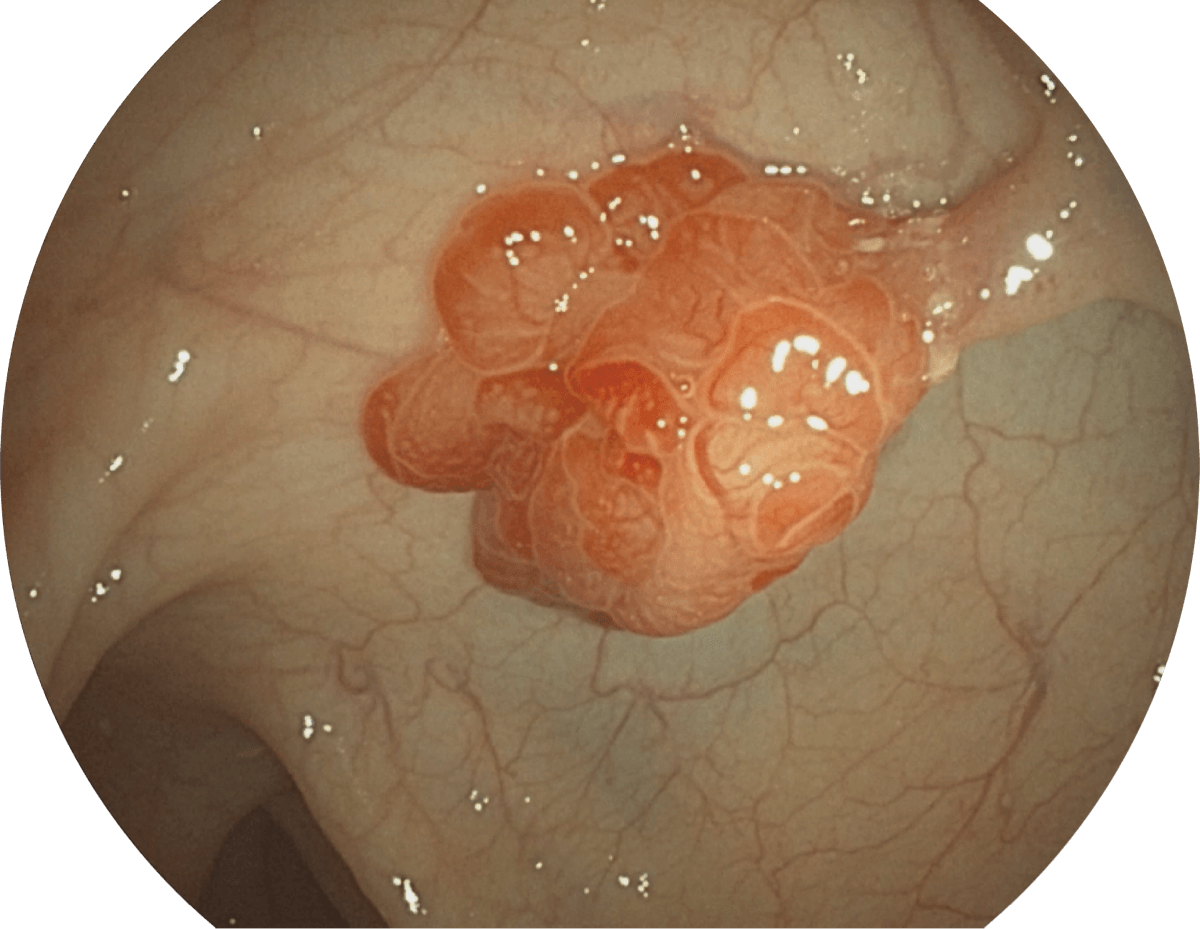

强调浅层黏膜结构的同时,保证照明亮度和提升浅层微血管与中层血管颜色对比度,病变边界更清晰。

• VIST